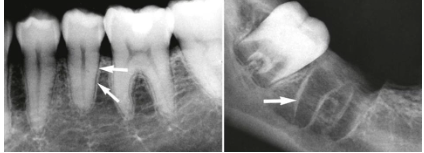

what are the numbers

alveolar bone

spongy (trabecular) bone

cortical plate

what are the arrows pointing to

lamina dura/cribriform plate

T/F: lamina dura/cribriform plate is compact

false, it has many perforations that allow it to have neurovascular bundles link to the PDL

describe what’s being circled

vertical bone loss: furcation involvement